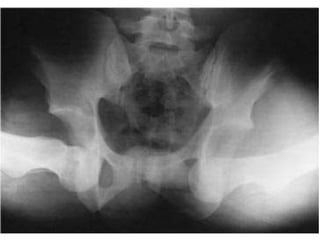

• Imagerie:

La Radiographie conventionnelle: La réalisation d’un bassin de face

est le minimum nécessaire et obligatoire chez un polytraumatisé,

surtout si celui-ci présente des troubles de la conscience.

Des clichés de profil ou de trois quarts sont réalisés au moindre

doute.

Il faut analyser la symétrie des interlignes coxofémoraux, le respect

du cintre cervico-obturateur, la position des hanches en rotation et

la taille respective des têtes fémorales (effet d’agrandissement). Il

faut également rechercher une lésion osseuse associée du bassin

ou de l’extrémité supérieure du fémur.